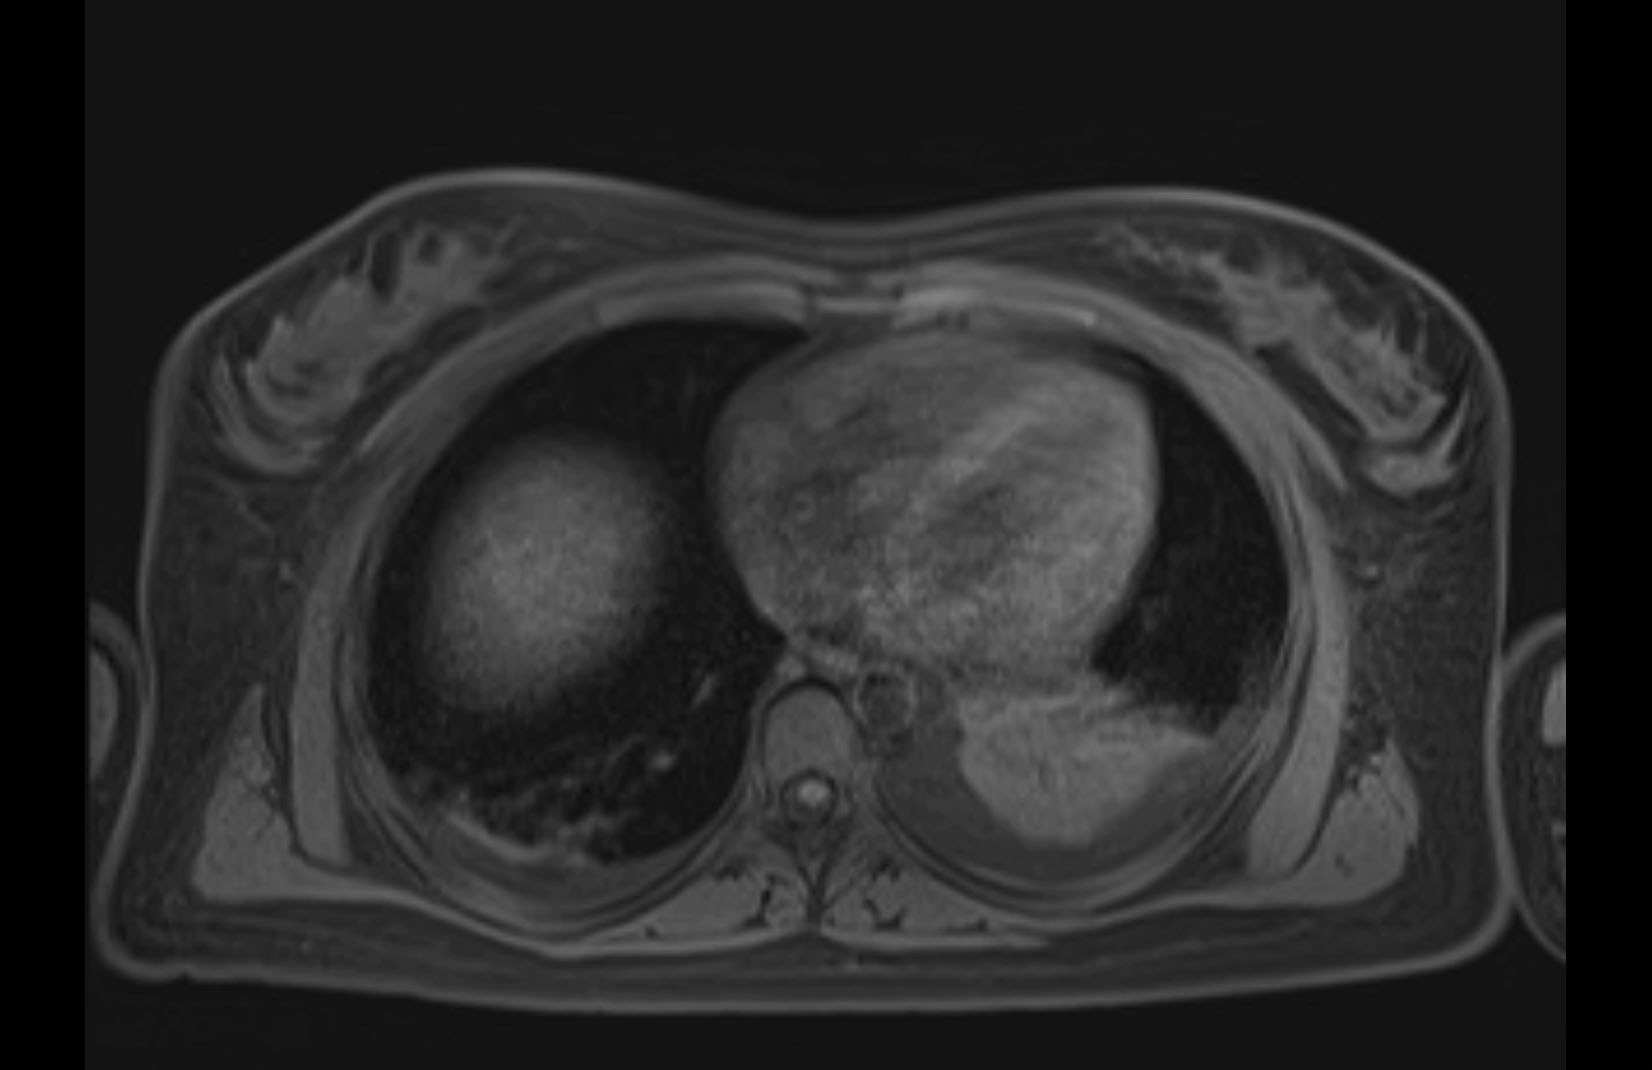

Imaging Analysis

Look through the patient's CT scan to identify any areas of concern for the necessary procedure.

MRI T1

MRI T2

Based on initial findings, which issue(s) would you be most concerned about?